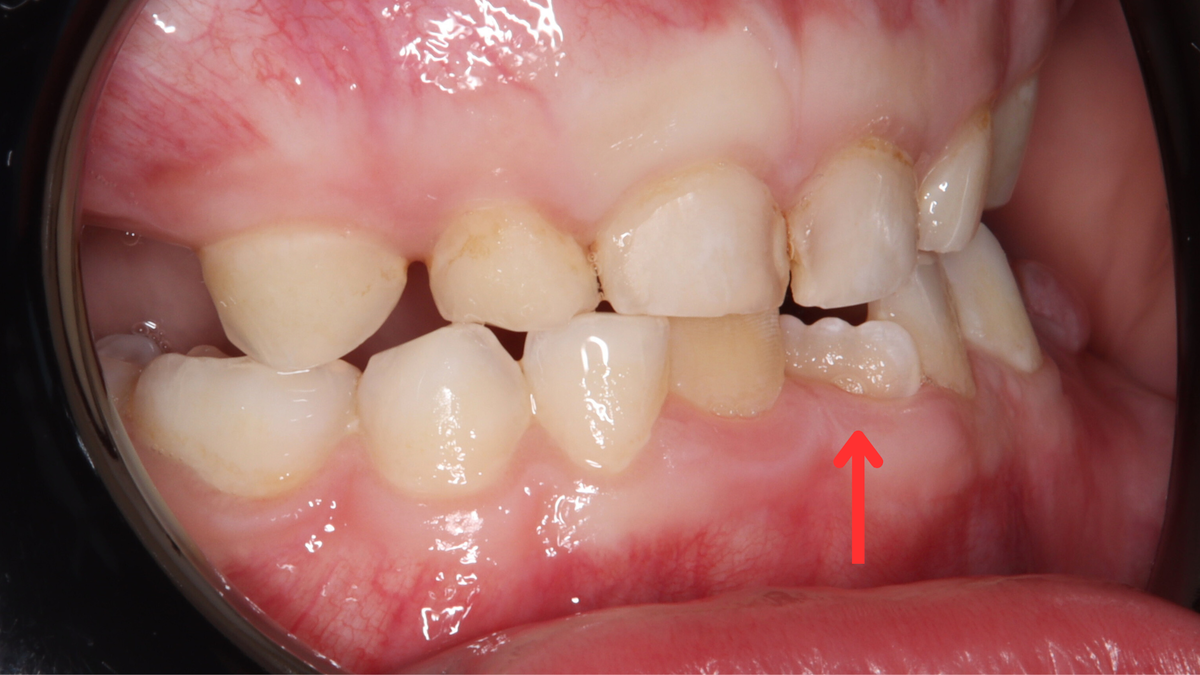

- В большинстве случаев тортоаномалия возникает у однокорневых зубов — в первую очередь у резцов и клыков верхней и нижней челюсти. Нередко аномалия встречается и у премоляров.

- Любая аномалия положения зубов может привести к негативным последствиям. Когда зубы стоят неровно — особенно если таких несколько и они повёрнуты под разными углами — между ними легко застревает пища, а качественно почистить такие участки становится крайне сложно.

В результате постоянно скапливается мягкий зубной налёт, который создаёт идеальную среду для размножения бактерий. Под налётом сначала появляются белые меловые пятна — признак деминерализации эмали. Со временем эмаль истончается, пятна увеличиваются, и на этом месте формируется кариозная полость.